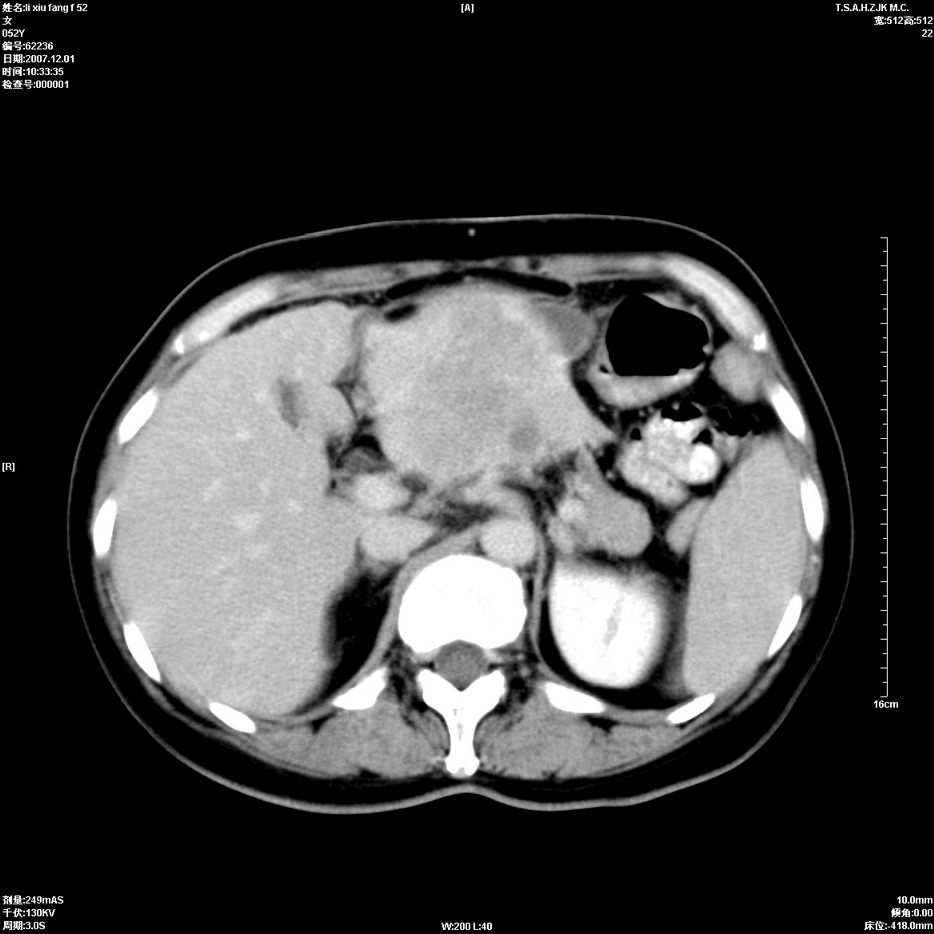

标题: CT12858:女,52岁,胎甲球蛋白861肝左叶占位,肝癌。下腔静 [打印本页]

标题: CT12858:女,52岁,胎甲球蛋白861肝左叶占位,肝癌。下腔静

肝左叶巨大低密度灶肿块,增强符合快进快出表现,有动静脉交通支;静脉期,下腔静脉内有充盈缺损,afp明显升高,支持肝癌并下腔静脉癌栓形成。

以下是引用拾荒者在2008-4-15 22:57:00的发言:[br]肝左叶巨大低密度灶肿块,增强符合快进快出表现,有动静脉交通支;静脉期,下腔静脉内有充盈缺损,afp明显升高,支持肝癌并下腔静脉癌栓形成。